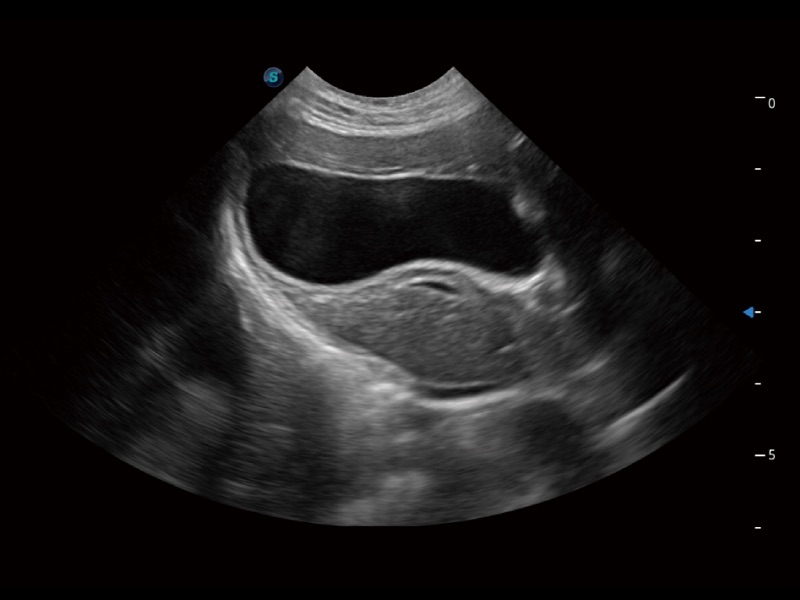

一键自动识别膀胱壁及自动测量膀胱容积,不受膀胱形状和大小的限制,帮助医生快速精准获得测量的数据。

能够基于左心室壁追踪和辛普森法,自动计算射血分数,支持多个可移动点描迹,与手动测量相比,极大节省了动物医生的时间和精力。

通过360度任意调节3条M型取样线,在同一心动周期上观察心脏不同位置的运动曲线,得到准确的心功能测量数据,有效评估心肌运动及左心室功能。

当心脏测量结果超出正常范围时,可实时预警提示动物医生,减少疾病漏诊概率。